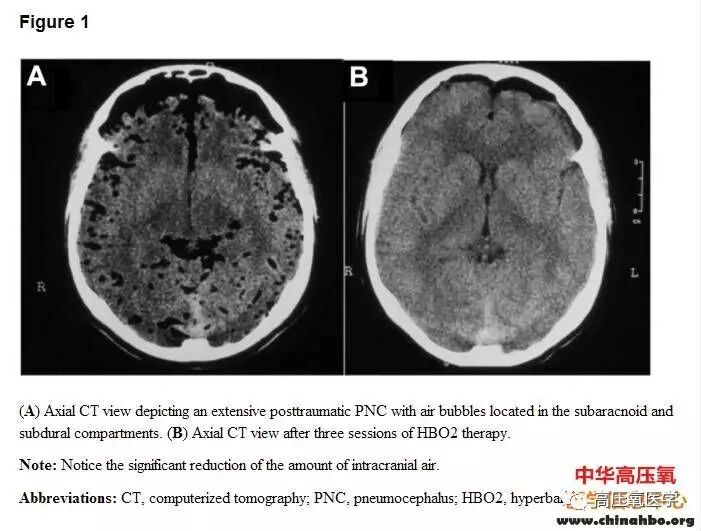

图片

气泡在蛛网膜下腔和硬脑膜下,3次高压氧治疗后